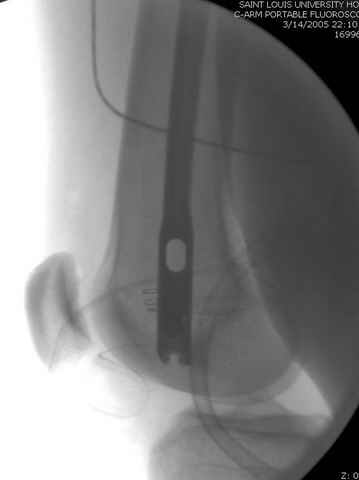

03.14.2005

больному 42, автоавария, политравма, открытая черепномозговая травма, безсознании, открытый перелом бедра, размозжение мягких тканей, дефект кожи на передней поверхности бедра около 13 см2 от ожога, компартмент синдром.

По поводу открытого перелома больной ургентно взят на ретроградное интрамедулярное штифтование, после рутинного дебрайдмента и фасциотомии на бедре и на голени.

Наблюдается службой травмы и нейрохирургии (ICP) Increased Intracranial Pressure by ventricular cateter

перелом бедра

интраоперационные